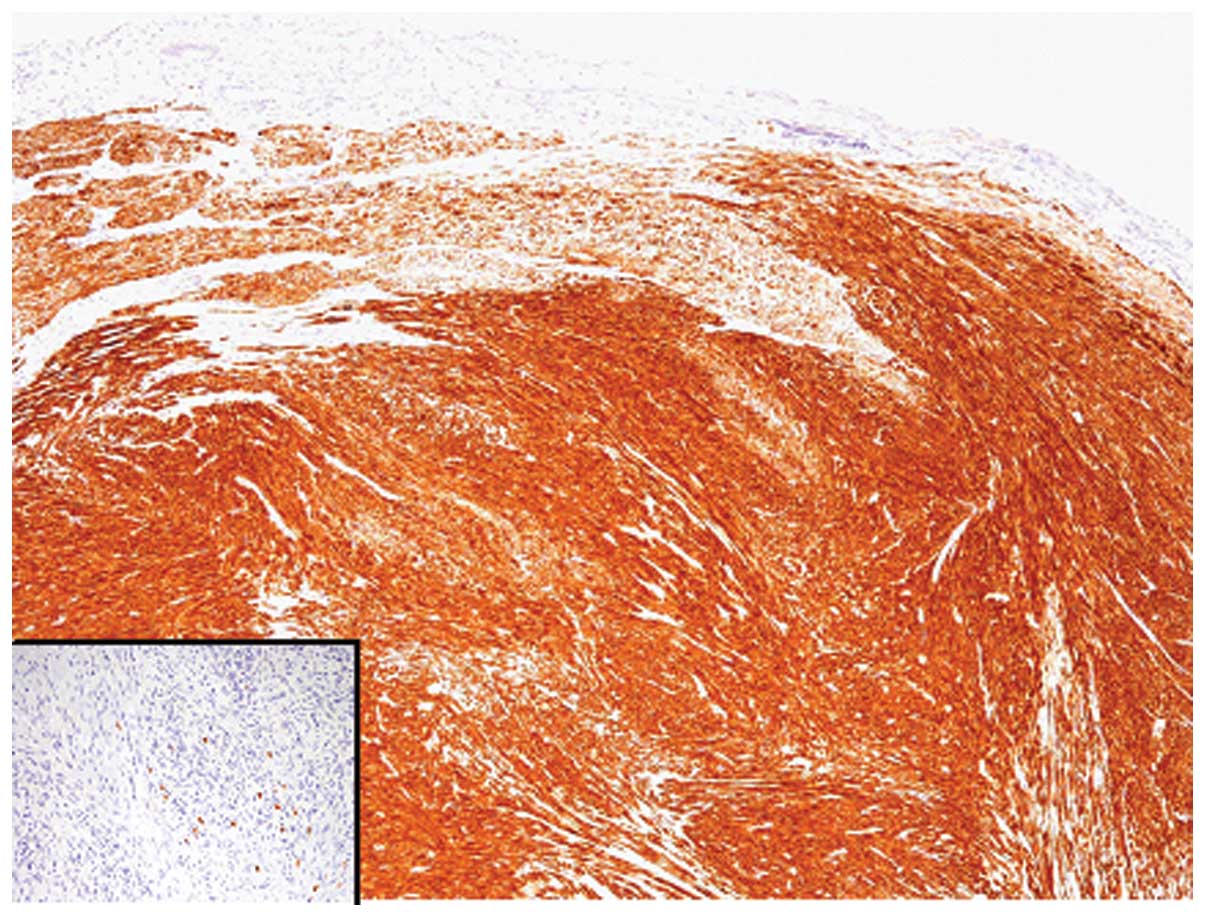

Mesenchymal tumor of the gallbladder is rare and the majority of cases present as sarcomas. Benign mesenchymal tumors of the gallbladder are extremely rare and to date, only one case of leiomyoma has been reported. In this report, we describe a second case of leiomyoma of the gallbladder, and discuss the differential diagnostic considerations. A 55‑year‑old female with metastatic gastrointestinal stromal tumors (GISTs) in the liver was identified to possess a tumorous lesion of the gallbladder. The patient had previously received a partial gastrectomy for GIST, and multiple liver metastases were revealed. Following surgery, imatinib was administered, and the liver metastatic lesions were stabilized. Histopathological analysis of the resected gallbladder specimens revealed that the nodule arose from the muscular layer, and was composed of spindle cell proliferation with eosinophilic cytoplasm and bland cigar‑shaped nuclei. Mitotic figures were rarely noted, and necrosis was not observed. Immunohistochemical analyses demonstrated that the tumor cells were positive for desmin and alpha‑smooth muscle actin, but negative for CD117 and CD34. In accordance with these results, a final diagnosis of leiomyoma of the gallbladder was made. The present case is unique since the patient possessed multiple metastatic GISTs in the liver, and the gallbladder nodule was preoperatively suspected to be a metastatic GIST. Leiomyoma of the gallbladder is extremely rare; however, it may be an underrecognized entity. Thus, it is important to differentiate leiomyoma from GIST to avoid unnecessary clinical follow‑up and treatment.